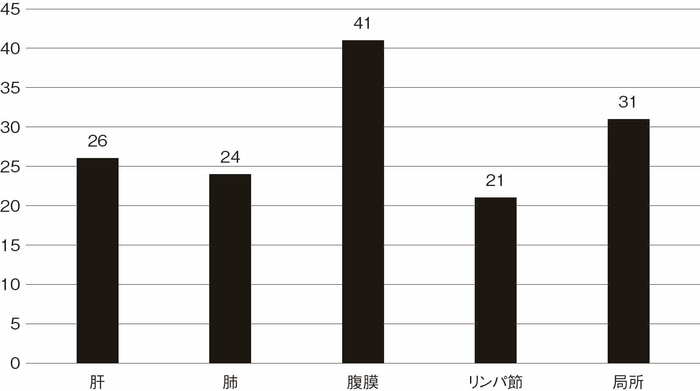

プロジェクト研究におけるCD関連大腸癌との比較では,Stage 0, 1症例の全生存は同等であったが,Stage 2, 3, 4症例においてはUC関連大腸癌の全生存はCD関連大腸癌に比べて有意に良好であった1)(各論Ⅱ,CD関連消化管腫瘍,5.予後を参照)。UC関連大腸癌とCD関連大腸癌の予後を直接比較した論文は少ないが,3論文のメタアナリシスの結果でも同様にUC関連大腸癌の全生存はCD関連大腸癌よりも有意に良好である結果が示されている3)。 - 術後再発形式

プロジェクト研究で集積された症例の切除後における部位別再発症例数(観察期間中央値46カ月)を図21に示す。腹膜播種再発が最も多く,2番目に多いのは局所再発であった1)。大腸癌研究会による全大腸癌の全国登録の成績では肝再発が最も多く,次いで肺再発であり,いずれも腹膜再発や局所再発の約3倍の頻度であるが,プロジェクト研究のUC関連大腸癌においては腹膜播種や局所再発よりも少なかった。腹膜播種の治療成績は肝転移や肺転移に比べて不良であることが示されており4),UC関連大腸癌の予後が散発性大腸癌よりも不良である一因となっていることが推測される。

図21 UC関連大腸癌再発部位